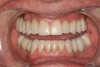

Fig 4. Diagnostic provisionals for functional rehabilitation.

Figure 4